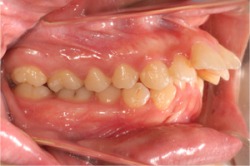

引用元:アイウエオ矯正歯科(https://www.aiueo-kyousei.com/wp/case/database.cgi?cmd=dp&num=326)

前歯が前方に向けて突き出す形で生えていたため、ワイヤー矯正で矯正した症例です。症状に合わせてワイヤーを曲げ、噛み合わせも考えながら矯正されています。